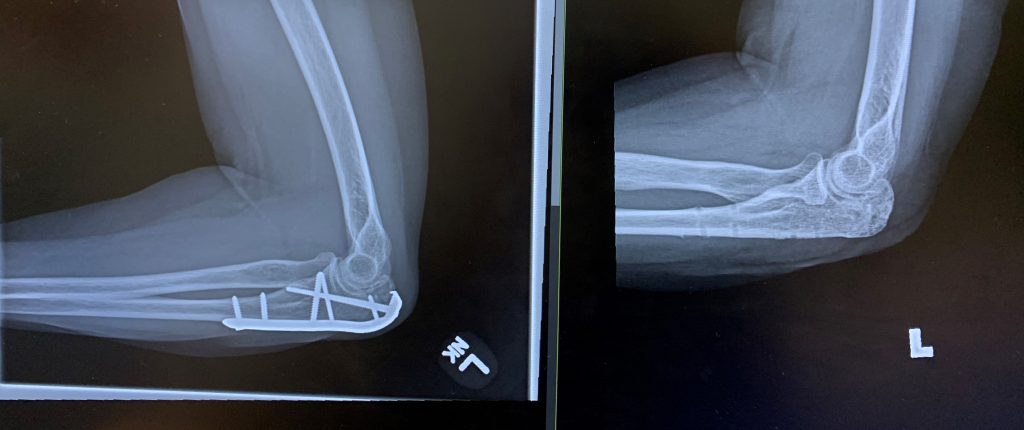

The tip of my elbow broke off when I fell from my bicycle onto my bent elbow. The pain was so extreme I struggled to remain conscious and didn’t realize I’d also fractured two knuckles of my other hand. An ambulance brought me to a local hospital, where admission and surgery was recommended. I called Dr. Joseph Lane, who treats me for osteoporosis, for advise. It was a Saturday evening but he called me right back. He offered admission to NYP Hospital. I will be forever grateful to Dr. Lane for guiding me into the superb hands of orthopedic trauma surgeon Dr. Daniel Dziadosz. Dr. Dziadosz fixed my elbow (literally!) and carefully monitored my progress afterwards. He helped me navigate my return to work and life in general. He was supportive and encouraging throughout my recovery. Dr. Dziadosz operated on my elbow a second time recently to remove the hardware used for the repair a year and a half ago. This surgery was elective and considered together carefully. By Day 1 post-op I knew we’d made the right decision. Two weeks later, now that the stitches were removed and my recovery is progressing quickly, I am actually saddened to have no further reason to see Dr. Dziadosz again. Throughout this ordeal, it’s been easy to develop a warm relationship with him and his team (PA Austin Milan and, in the office, Eloina). Dr. Dziadosz is so smart, funny, engaging and just plain cool, my husband and I both will miss my office visits with him. If I ever have another broken bone, he’s the one I will go to. I’ve had seven other previous orthopedic surgeries to repair broken bones (knee and leg, foot, both shoulders, hand and wrist), from Vail, CO to Long Island, NY. HSS at NYP is the best. From the minute one walks in the door and all the way through to the end result, these affiliated hospitals run like well oiled machines, staffed by well trained and professional staff, with the best surgeons across the country. It makes a huge difference in one’s life. I’m so grateful to Dr. Dziadosz and Austin, Dr. Lane, the anesthesiologists, the hand OT, and nurses, all for their expert and compassionate care. It doesn’t get any better than this. I will be forever grateful!